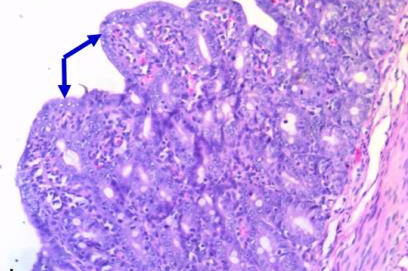

– Bệnh tích vi thể tập trung chủ yếu ở ruột non với lông nhung bị phá huỷ, tế bào biểu mô ruột thoái hoá, hoại tử, lông nhung ngắn lại và tù đầu. Bên cạnh đó bệnh tích vi thể kết hợp có thể do nhiễm khuẩn kế phát như sung huyết các mạch quản, thâm nhiễm tế bào viêm ở hạ niêm mạc.

Tỷ lệ dương tính với virus PED của lợn rừng con theo mẹ là 74,3% đối với mẫu ruột, hạch màng treo ruột và 54,3% đối với mẫu phân. Triệu chứng lâm sàng chủ yếu của lợn rừng mắc PED là ủ rũ, mệt mỏi, phân lỏng,tanh màu vàng, gầy gò, nằm chồng đống, nằm trên bụng mẹ, bỏ ăn, mắt trũng sâu, uống nước nhiều, lười bú thân nhiệt giảm, thở nhanh… Lợn chết xác gầy, da khô, nhăn nheo, dạ dày và ruột non căng phồng, thành mỏng, chất chứa màu vàng, lợn cợn. Bệnh tích vi thể điển hình ở đường tiêu hoá với lớp lông nhung bị phá huỷ, tế bào biểu mô thoái hoá, tế bào biểu mô thoái hoá, hoại tử tăng sinh. Kết quả nghiên cứu khẳng định lợn rừng nuôi cũng mắc dịch tiêu chảy do virus như cũng các giống lợn khác

Hình 2. Lông nhung tù đầu, các lông nhung dính lại với nhau, HE